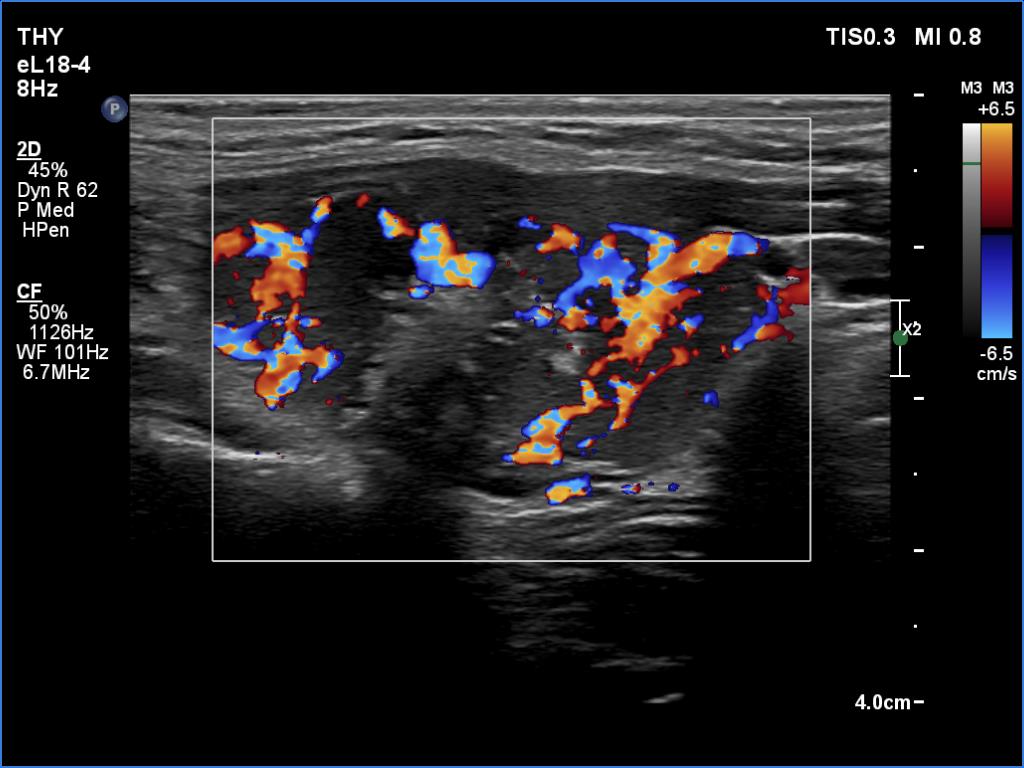

According to the palpable mass in the right submandibular area, there was a heterogeneous lesion which has hypoechoic and echonormal parts. The mass had irregular margins and showed vascularity. The distance between the submandibular mass and the thyroid was more than 35 mm.